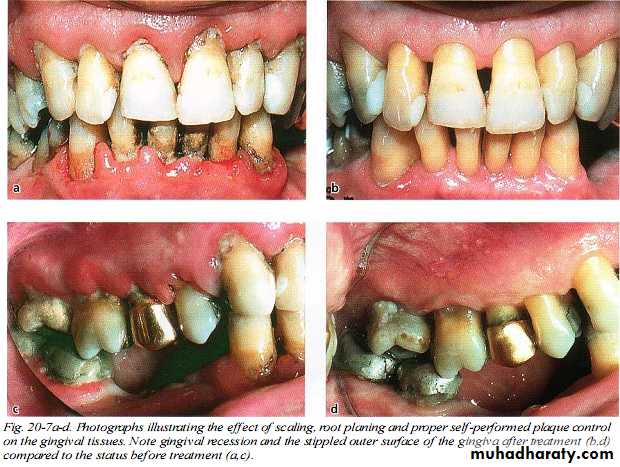

Scaling is the process by which biofilm and calculus are removed from both supragingival and subgingival tooth surfaces. Root planing is the process by which residual embedded calculus and portions of Cementum are removed from the roots to produce a smooth, hard, clean surface.

Scaling and root planing are not separate procedures; all the principles of scaling apply equally to root planing.

Scaling and root planing should not be viewed as separate procedures unrelated to the rest of the treatment plan.

Sickles, curettes, and ultrasonic and sonic instruments are most often used for the removal of supra gingival calculus; hoes and chisels are less frequently used.

Sub gingival scaling and root planing are much more complex and difficult to perform than supra gingival scaling